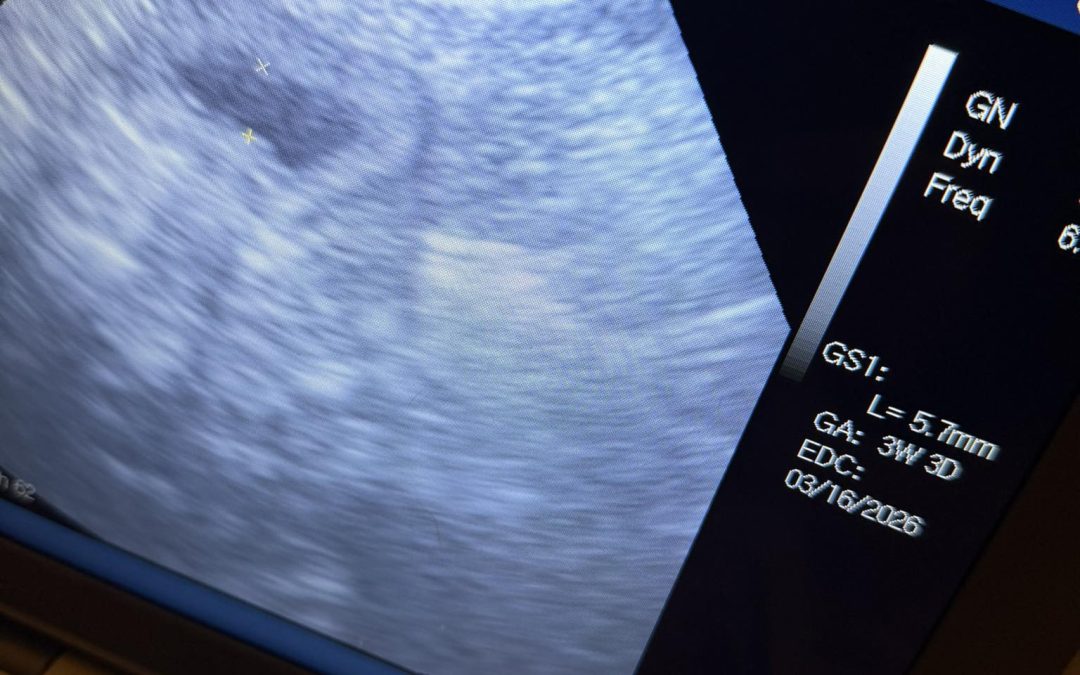

Service: Preston Mobile Dog Fertility Location: Preston ,  Lancashire How We Helped: Confirmation ultrasound scan carried out on a mobile visit in Preston this evening On finding out this girl could be only about 3 weeks pregnant Sacs could be seen, but no embryos...